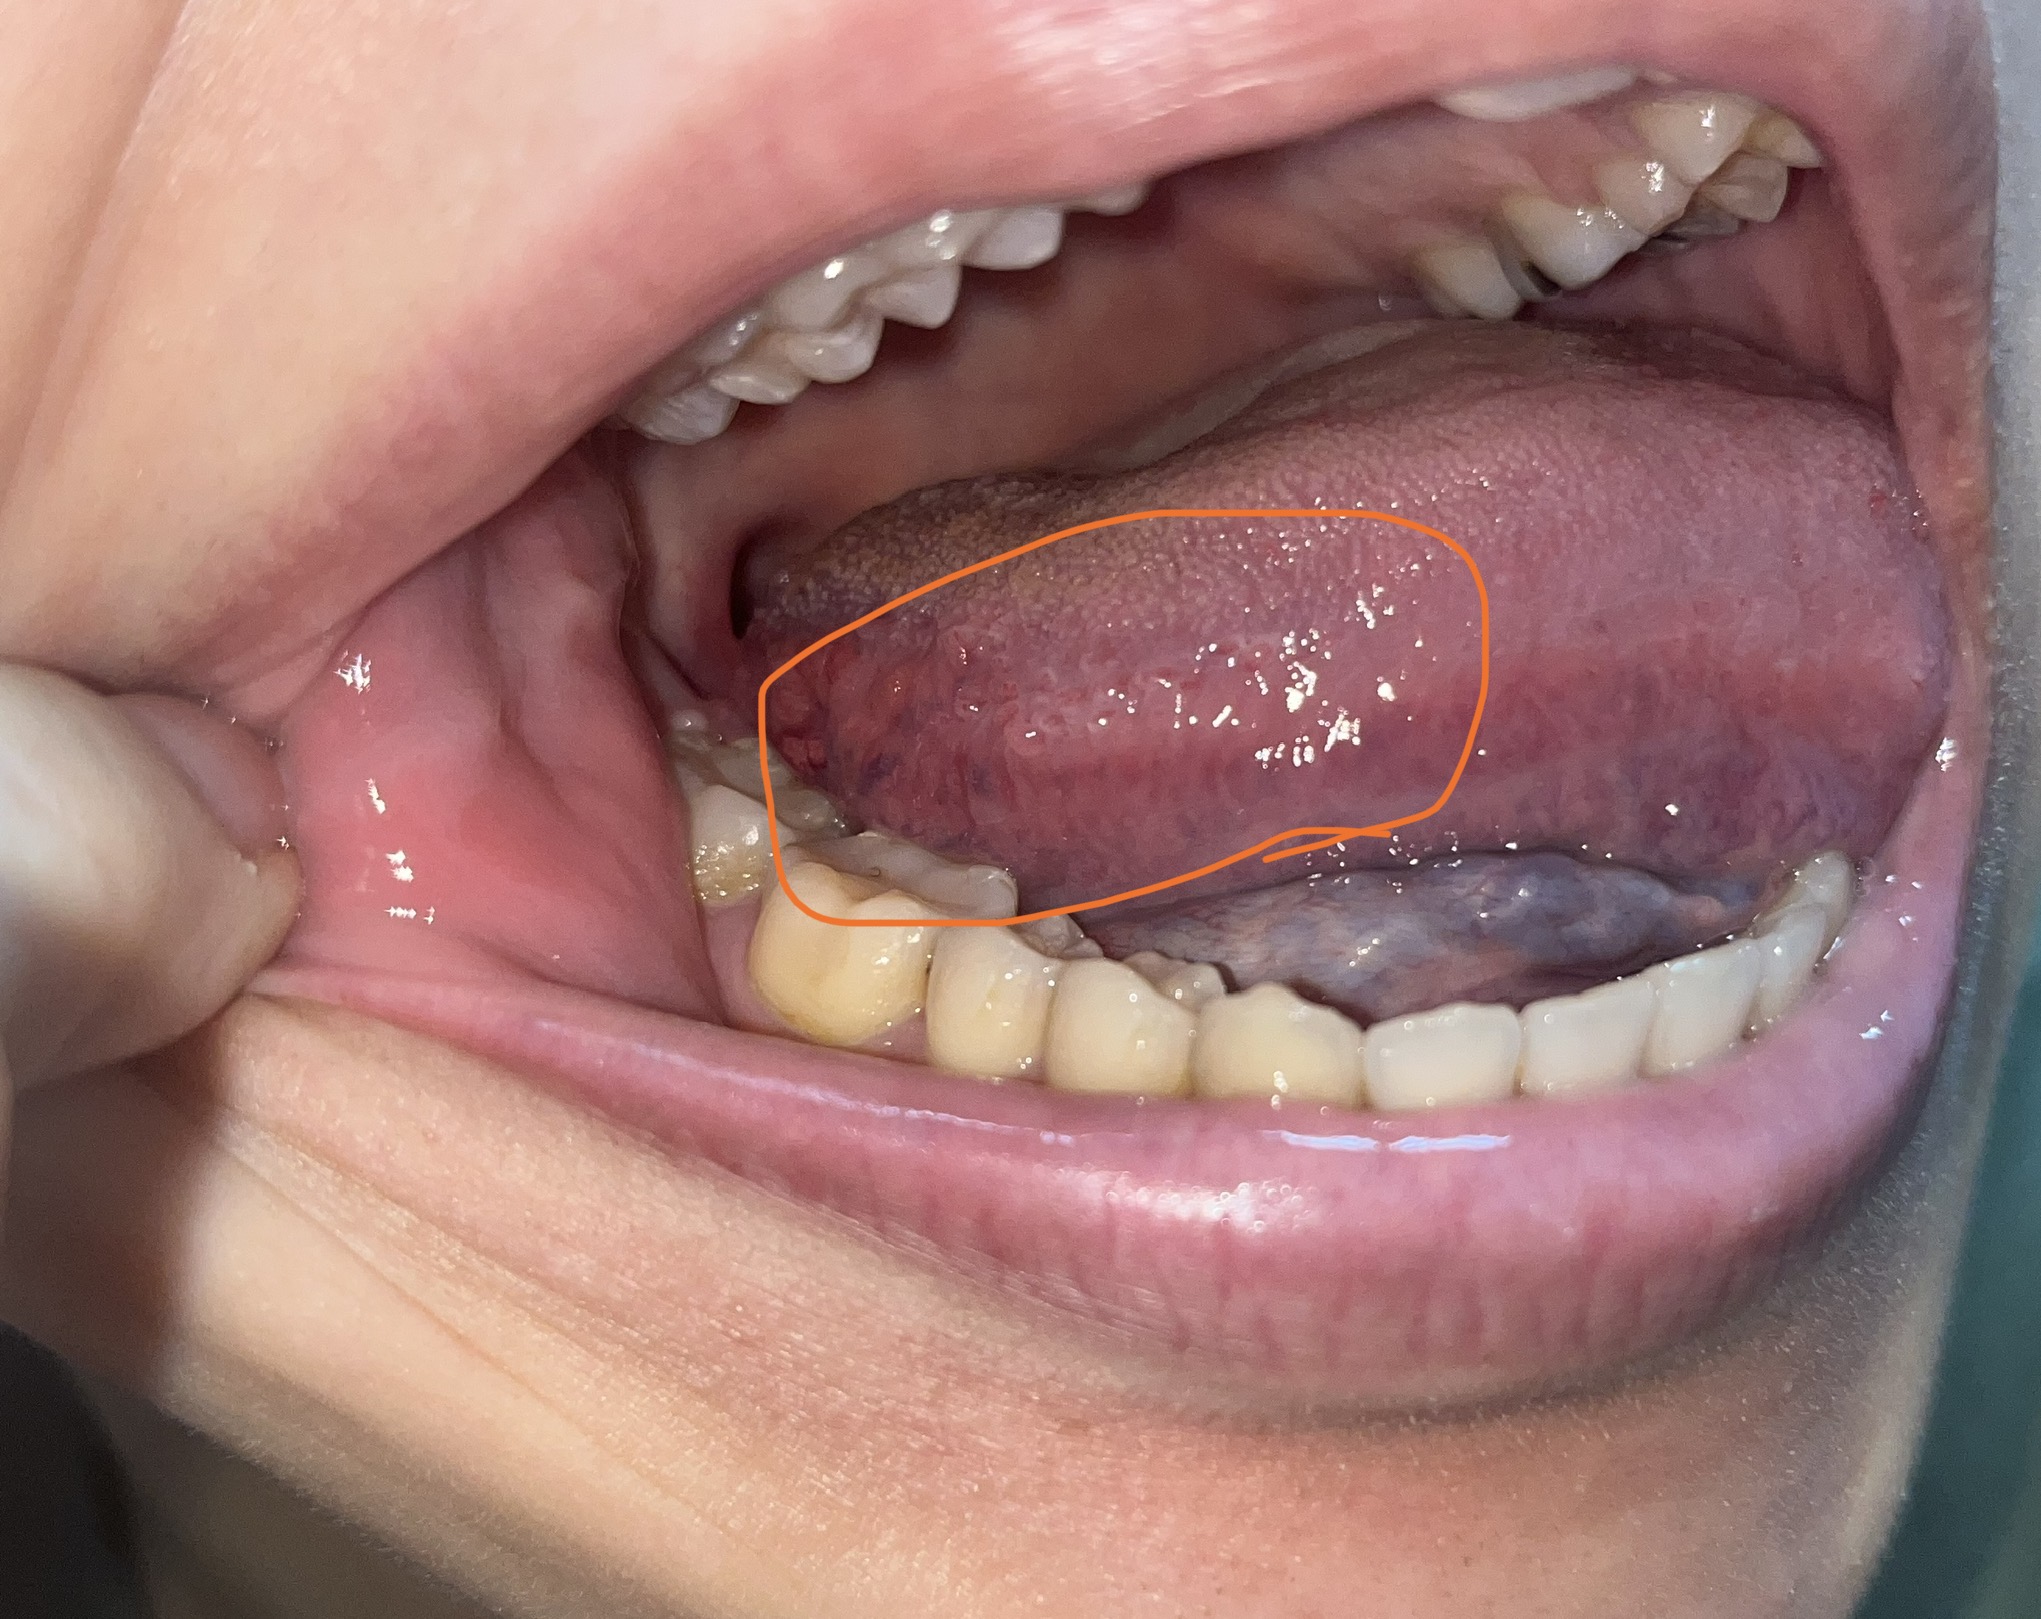

口内炎が痛くない!?舌癌?口内炎?正しい見分け方ハイライフグループ。

舌の口内炎と舌癌はどう違うのか口腔外科医のお役立ちコラム 東京銀座シンタニ歯科口腔外科クリニック。

舌の右側側面、丸で囲った場所がよく痛みます。口腔外科.com-提供は安原歯科医院。

ベロにしこりがある!これって舌癌?舌癌の5大症状 – さいたま市岩槻区審美歯科のスワンデンタルクリニック。